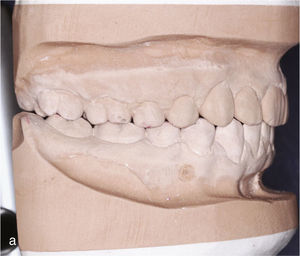

El paciente se presentó en nuestro centro con el siguiente cuadro: dentición permanente con proinclinación de dientes anteriores y desviación de la línea media, diente 53 persistente, dientes 13 y 23 elevados y desplazados hacia vestibular, curva de Spee marcada con extrusión del sector anteroinferior, dientes rotados y apiñados en maxilar y mandíbula, clase II de Angle con un resalte de 4mm y sobremordida de 0mm, además de ausencia de guía canina (figs. 13a a 13c y 14a a 14e).

El plan de tratamiento incluyó el establecimiento de una clase I de Angle con sobremordida horizontal y vertical fisiológicas mediante la distalización del sector posterosuperior, con corrección de los caninos superiores y aseguramiento de una guía canina. Las arcadas se dotaron además de una apariencia armoniosa eliminando la giroversión y los apiñamientos mediante la reducción del esmalte interproximal y el ajuste de las líneas medias. El paciente optó por un tratamiento con el sistema Invisalign alternativo a la aparatología fija con brackets. Se colocó un atache rectangular vertical en los dientes 13 y 23 y, en el curso del tratamiento, también en los dientes anterosuperiores y en el diente 43. Además durante todo el tratamiento el paciente llevó elásticos de clase II en ambos lados, del diente 14 al diente 46 y del diente 24 al diente 36 para obtener el anclaje necesario durante la distalización. La figura 15 muestra la situación intraoral de un caso similar con brackets en los dientes 13 y 46. En la zona de los brackets se acortó el alineador. Además de los alineadores se utilizaron elásticos de clase II del diente 13 al diente 46.